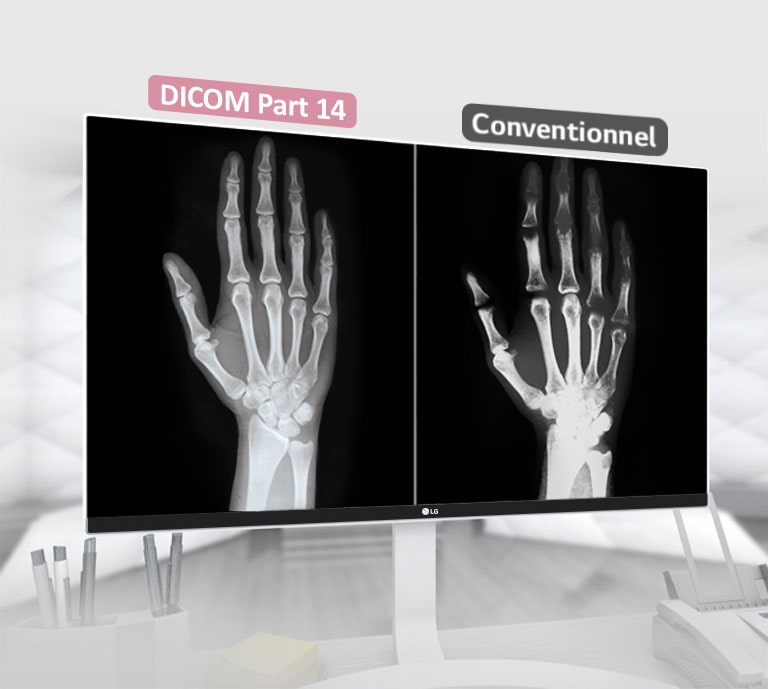

*DICOM (Digital imaging and Communications in Medicine):

Une norme s'appliquant aux caractéristiques des teintes de l'échelle des gris des moniteurs utilisés dans le secteur médical.

Conforme DICOM

OUI